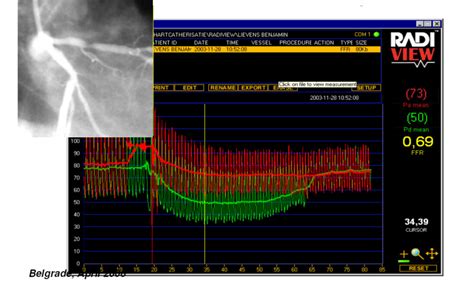

4. Calculating the FFR: During hyperemia, the pressure sensor measures the pressure on both sides of the blockage. The FFR is calculated as the ratio of the pressure after the blockage to the pressure before the blockage. So, it’s a simple division: Pressure Downstream / Pressure Upstream.

5. Interpreting the Results: This is where the magic happens. The FFR value is a number between 0 and 1. Here’s what it means:

• FFR > 0.80: This usually means the blockage isn’t significantly affecting blood flow. You might not need a stent or angioplasty, and medication might be enough.

• FFR ≤ 0.80: This suggests the blockage is significantly reducing blood flow. In this case, a procedure to open the artery, like angioplasty with stenting, is often recommended to improve blood flow and reduce symptoms.